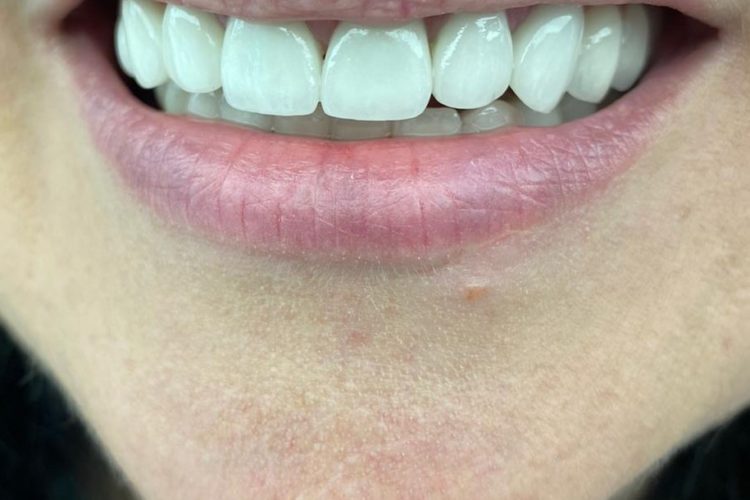

Pacienta in varsta de 52 de ani s-a prezentat in clinica noastra aflandu-se in cursul unui tratament implanto-protetic inceput in alta clinica. Pentru realizarea unor lucrari echilibrate ocluzal i s-a propus si realizat temporizare prin lucrari de PMMA (foto 3 si 4). Dupa 6 luni  s-au  realizat lucrari definitive din ceramica pe zirconiu (foto 5-10).